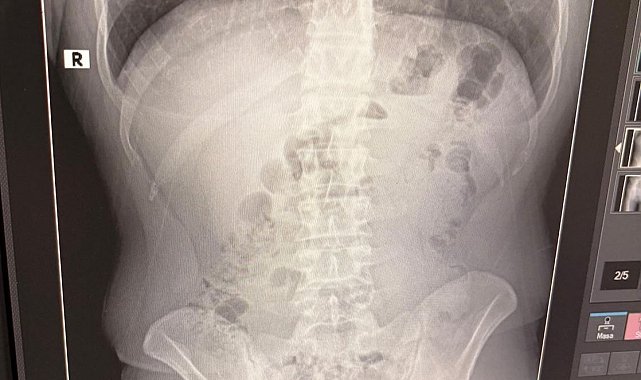

Adreste yapılan arama sırasında ekipler, şüphelilerden birinin üstünde 1 adet kapsül ele geçirdi. Şüphe üzerine tüm şüpheliler hastaneye götürüldü ve yapılan röntgen kontrollerinde 3 kişinin midelerinde kapsül içine gizlenmiş metamfetamin tespit edildi.

Hastanede tedavi altına alınan şüphelilerin vücudundan kapsüller çıkarılırken, adreste ele geçirilenlerle birlikte toplam 1 kilo 516 gram metamfetamin ele geçirildi.